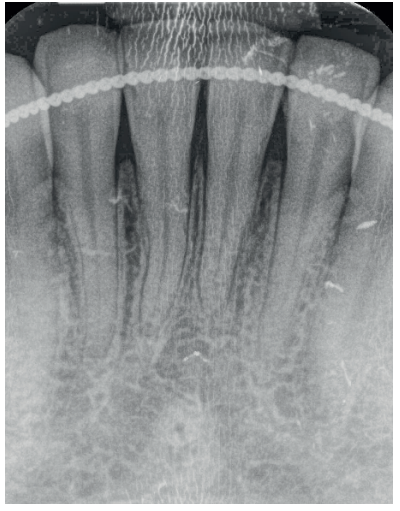

Mujer de 23 años que acudió a nuestra consulta debido a la presencia de múltiples recesiones gingivales desde el diente 32 al 42. La paciente refiere que nota sus dientes más largos, no presenta problemas de hipersensibilidad y había terminado el tratamiento ortodóncico hacía 1 año. La historia médica de la paciente no mostraba datos relevantes. No informó de alergias y no tomaba medicación de ningún tipo. El examen clínico periodontal reveló múltiples recesiones gingivales vestibulares que afectaban a los dientes 32, 31, 41 y 42 (Figura 9), con ausencia de tejido queratinizado apical a las recesiones de los dientes 31 y 32. Tras el estudio radiográfico (Figura 10) se observa pérdida ósea horizontal leve entre los incisivos inferiores (clase III de Miller y RT2 de Cairo).